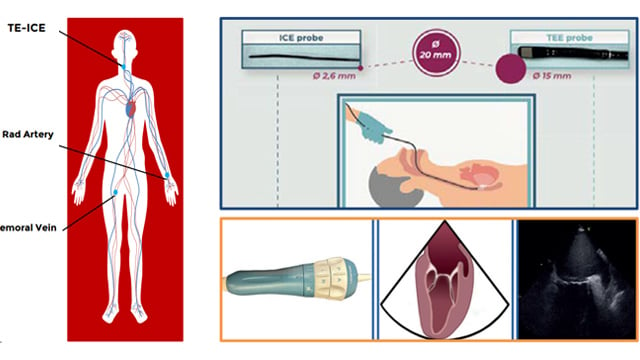

Left atrial appendage occlusion

17 Nov 2025 – From PCR London Valves 2025

This session focuses on the complexities and innovations in left atrial appendage occlusion (LAAO) procedures. It covers transesophageal ICE monitoring, challenges posed by existing atrial septal occluders, combined surgical and percutaneous approaches, and the practical experience with the Ultraseal device. These insights advance understanding of procedural...